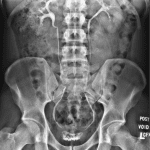

Age: 16

Sex: Female

Indication: Right flank pain

Findings

- Nonobstructive bowel gas pattern

- No abnormal intraabdominal mass effect

- Irregular calcification measuring approximately 4 mm overlying the expected location of the right ureterovesicular junction

Diagnosis

- Ureterovesicular junction (UVJ) stone

Nonobstructive bowel gas pattern.

No abnormal intraabdominal mass effect.

Irregular calcification measuring approximately 4 mm overlying the expected location of the right ureterovesicular junction. This calcification could alternatively be in the bladder or fecal stream. Consider noncontrast CT of the abdomen and pelvis for further evaluation.